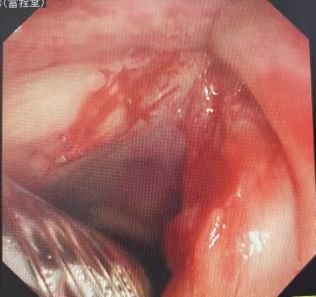

在充分評(píng)估支氣管鏡檢查風(fēng)險(xiǎn)后,首先在局麻下行電子支氣管鏡檢查:右側(cè)聲帶前中1/3可見(jiàn)腫瘤組織致喉狹窄。活檢組織病理證實(shí)為“高分化鱗癌”。因家屬有強(qiáng)烈的治療愿望,孫主任組織全科再次評(píng)估麻醉手術(shù)風(fēng)險(xiǎn)。患者重點(diǎn)、難點(diǎn)在于高齡,術(shù)中麻醉風(fēng)險(xiǎn)高,容易出現(xiàn)麻醉意外事件,難以耐受聲帶腫瘤切除并重建手術(shù)。隨后及時(shí)

一定時(shí)機(jī)。經(jīng)過(guò)充分討論后決定在全麻、氣管插管下,經(jīng)氣管鏡下介入方法完成局部手術(shù)切除治療。隨后在我科內(nèi)鏡室嚴(yán)密生命體征監(jiān)測(cè)及呼吸機(jī)支持條件下,在氣管插管后進(jìn)入電子支氣管鏡,針對(duì)右側(cè)聲帶腫物準(zhǔn)確快速清除,并局部創(chuàng)面的凍融治療。整個(gè)操作過(guò)程時(shí)間時(shí)間短、出血少,患者蘇醒快,氧合及生命體征穩(wěn)定。此次麻醉科、